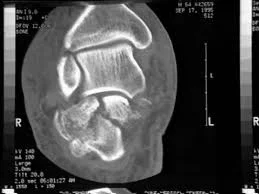

Advanced Imaging

- CT Scan:

- In complex and intra-articular fractures

- In spine

- In pelvic and acetabular fractures

- In calcaneal fractures